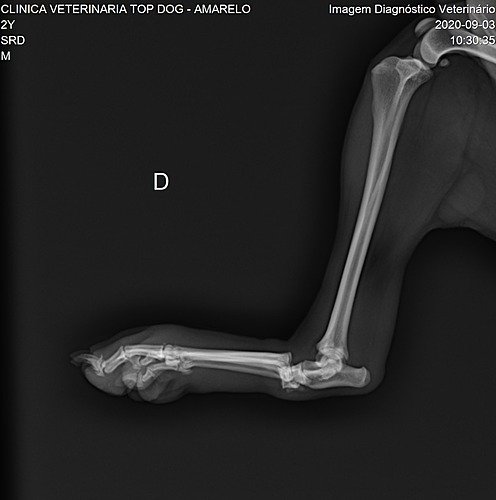

Meu nome é Peladinho, e me meti em confusão na rua brigando com outros 5 cães, na verdade não sei o que aconteceu, mas eles estavam me puxando de um lado para outro. Para minha sorte, quem me ajudou na Rua foram duas moças que estavam passando por ali nesse momento muito difícil para mim, pois ninguém mais conseguiu me ajudar. Eu senti muita dor, e estou muito machucado, então elas me levaram ao medico para que eu pudesse ser examinado, com a briga acabei tendo uma luxação articular, (fratura de Lisfranc) no meu pezinho, e agora só poderei andar fazendo uma cirurgia que precisa de pinos, e que é muito cara. Por isso preciso da ajuda de vocês pra fazer essa cirurgia o mais rápido possível, pois posso piorar. Como não tenho lar, essas moças estão me ajudando com essa vaquinha para poder arrecadar esse dinheirinho.

Deixo as imagens dos exames e o valor do procedimento, no valor de 3.500 já estou contando a medicação pós cirúrgica e as taxas cobradas para poder postar essa vaquinha.